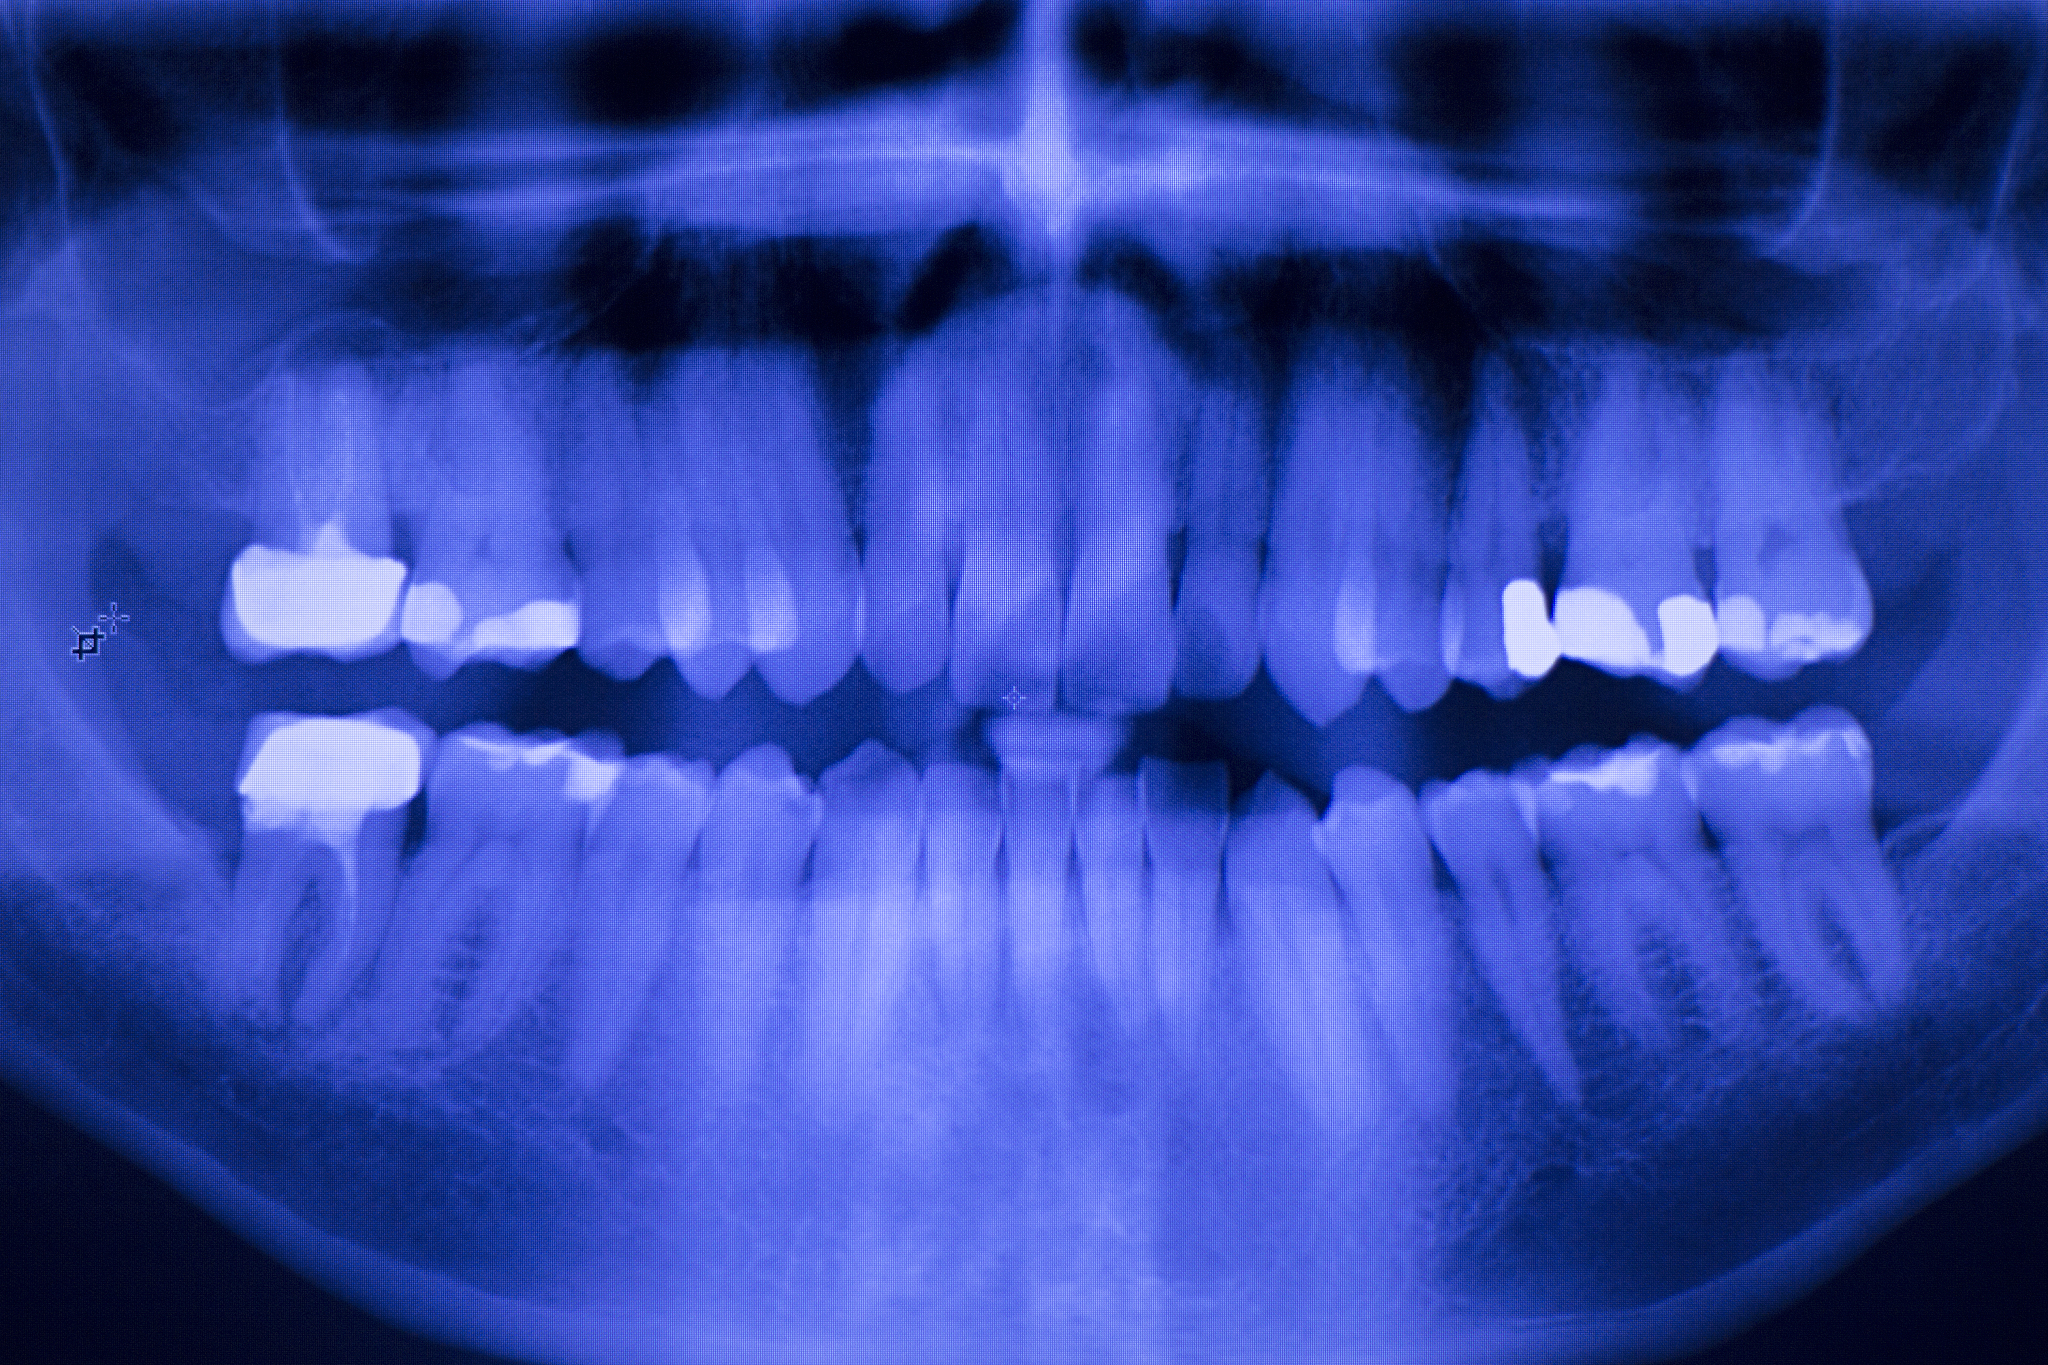

'口腔医学专业'是一门综合性的学科,涵盖口腔内科、口腔外科、口腔修复、口腔预防等多个方面。在现代医学中,口腔医学的地位越来越重要,因为口腔是人体健康的重要组成部分。昆明医科大学的口腔医学专业致力于培养全面发展、具有扎实理论基础和过硬临床技能的口腔医学人才。

昆明医科大学口腔医学专业拥有一流的教学设备和实验室,为学生提供了良好的学习环境。该校还积极开展科研工作,取得了一系列的科研成果,为口腔医学发展做出了贡献。